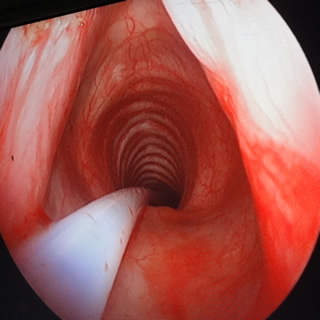

Enseñanza práctica de Fibrobroncoscopía en maniquíes y simulación en diferentes situaciones clínicas en dispositivo portátil ORSIM. Método que nos muestra cómo manejar situaciones complejas y poco frecuentes en la práctica clínica para el manejo de la vía aérea difícil, en el simulador ORSIM, creado por el Dr. Paul Baker.